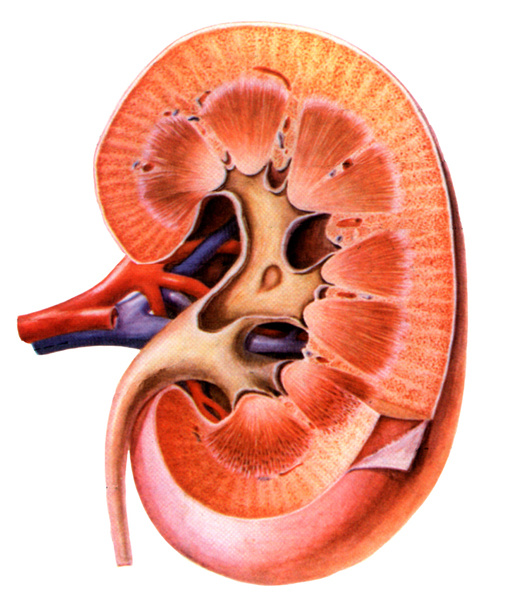

8 泌尿系统疾病

8.4 素材资源